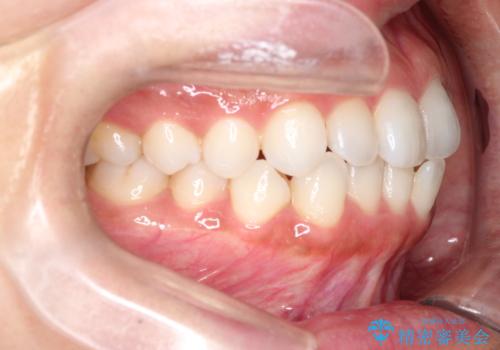

前歯の叢生を非抜歯で改善|インビザライン+IPR・遠心移動・FIX保定

- 前歯部のガタガタ(叢生)を非抜歯で改善するため、インビザラインによるマウスピース矯正を計画しました。抜歯は行わず、歯間をわずかに削るIPR(ディスキング)と奥歯を後方に移動させる遠心移動を併用して、歯を並べるスペースを確保します。歯列が整った後は、FIXリテーナー(固定式保定装置)で後戻りを防止し、安定した歯並びを維持します。

歯を抜きたくないというご希望に応え、インビザラインを用いて非抜歯で歯列を整えました。前歯に必要なスペースを確保するため、歯間をわずかに削るIPRと奥歯を後方に移動する遠心移動を組み合わせました。これにより自然で美しい歯並びを実現。治療終了後は、歯の裏側に目立たないFIXリテーナーを装着し、歯列の後戻りを効果的に防ぎました。患者様は治療中も審美的にストレスなく過ごされ、満足度の高い結果を得られました。